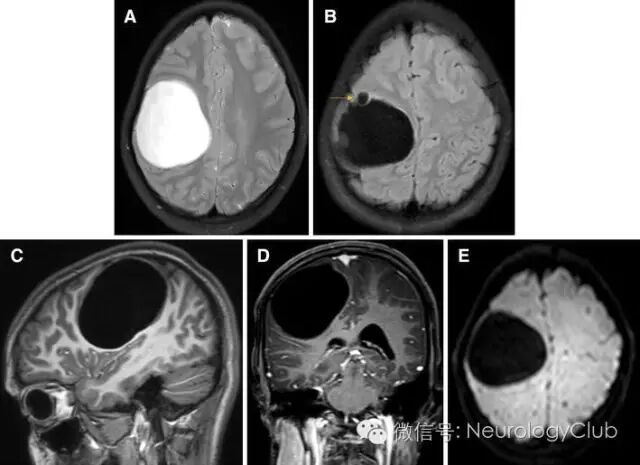

14岁女孩,表现为颅内压升高症状。头颅MRI提示右侧额顶叶边界清楚的T2高信号大囊性病变,壁薄,伴有前部子囊(图1)。病灶周围水肿不明显。未见胸部或腹部类似受累证据。

(图1:T2WI[A],FLAIR[B]和DWI[E]提示边界清楚的右侧额顶叶囊性病变,与脑脊液等信号,无病灶周围水肿,未见弥散受限;FLAIR上可见前部子囊[黄箭];矢状位T1WI[C]和T1增强[D]对比未见明显强化)